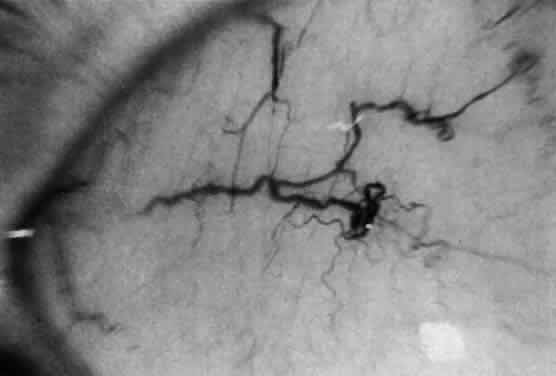

Corneal clouding (Fig. 10), hyperopic astigmatism, and a mild retinopathy with surface-wrinkling maculopathy (Fig. 11) appear to be the constant ocular triad.75 Some patients have retinal vascular tortuosity, optic nerve head swelling (Fig. 12), visual field defects, and abnormalities in color vision. Visual complaints are uncommon.

Fig. 11. Surface-wrinkling maculopathy in a patient with mucolipidosis III. (Traboulsi E, Maumenee I: Ophthalmologic findings in mucolipidosis III. Am J Ophthalmol 102:529, 1986)

Fig. 12. Optic nerve head swelling in a patient with mucolipidosis III. (Traboulsi E, Maumenee I: Ophthalmologic findings in mucolipidosis III. Am J Ophthalmol 102:529, 1986)